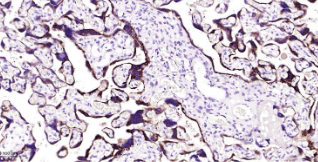

Immunohistochemical analysis of paraffin embedded human placenta tissue slide using IHC0394H (Human hCG beta IHC Kit).